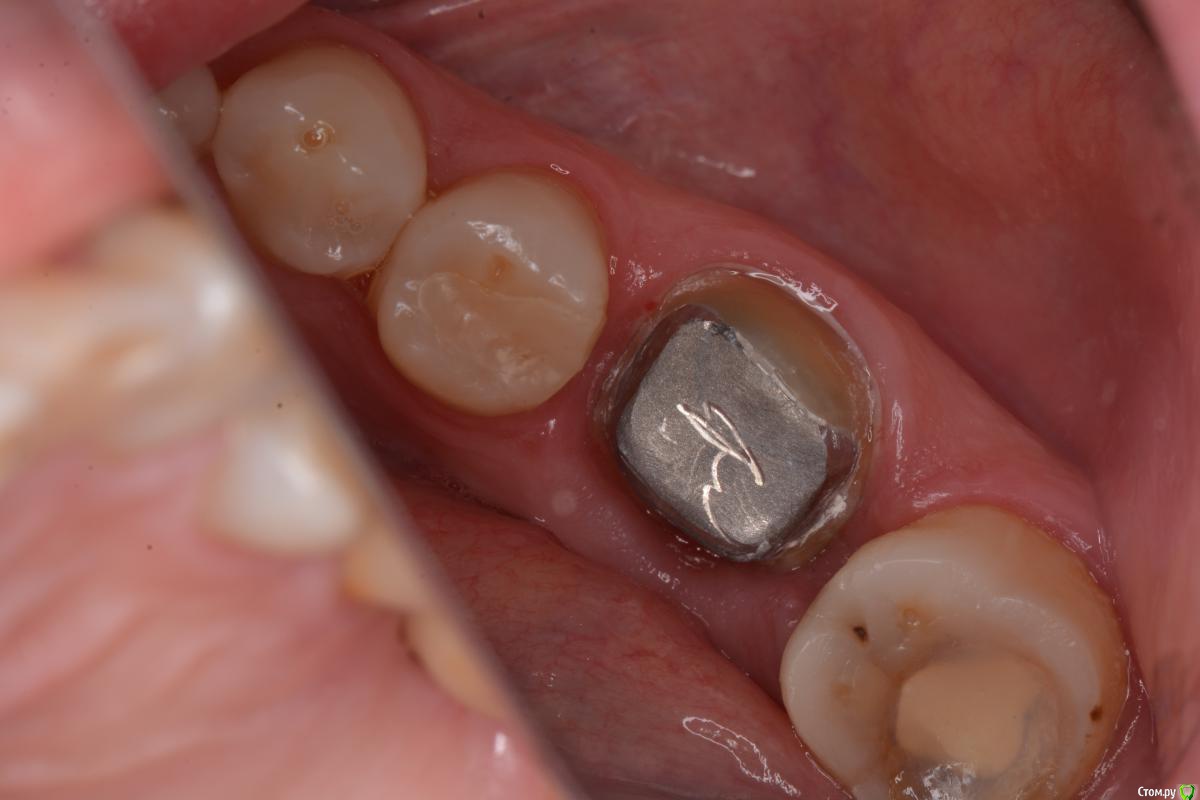

togrul Опубликовано 3 марта, 2015 Поделиться Опубликовано 3 марта, 2015 (изменено) Добрый вечер. Снимки в день сдачи. Изменено 3 марта, 2015 пользователем togrul 4 1 Ссылка на комментарий

Ibulat_1986 Опубликовано 3 марта, 2015 Поделиться Опубликовано 3 марта, 2015 Добрый вечер. Снимки в день сдачи. на вкладке ваша подпись? лол Ссылка на комментарий

togrul Опубликовано 4 марта, 2015 Автор Поделиться Опубликовано 4 марта, 2015 на вкладке ваша подпись? лол Нет случайно так получилось. Увидел на фотографиях потом. ) 1 Ссылка на комментарий